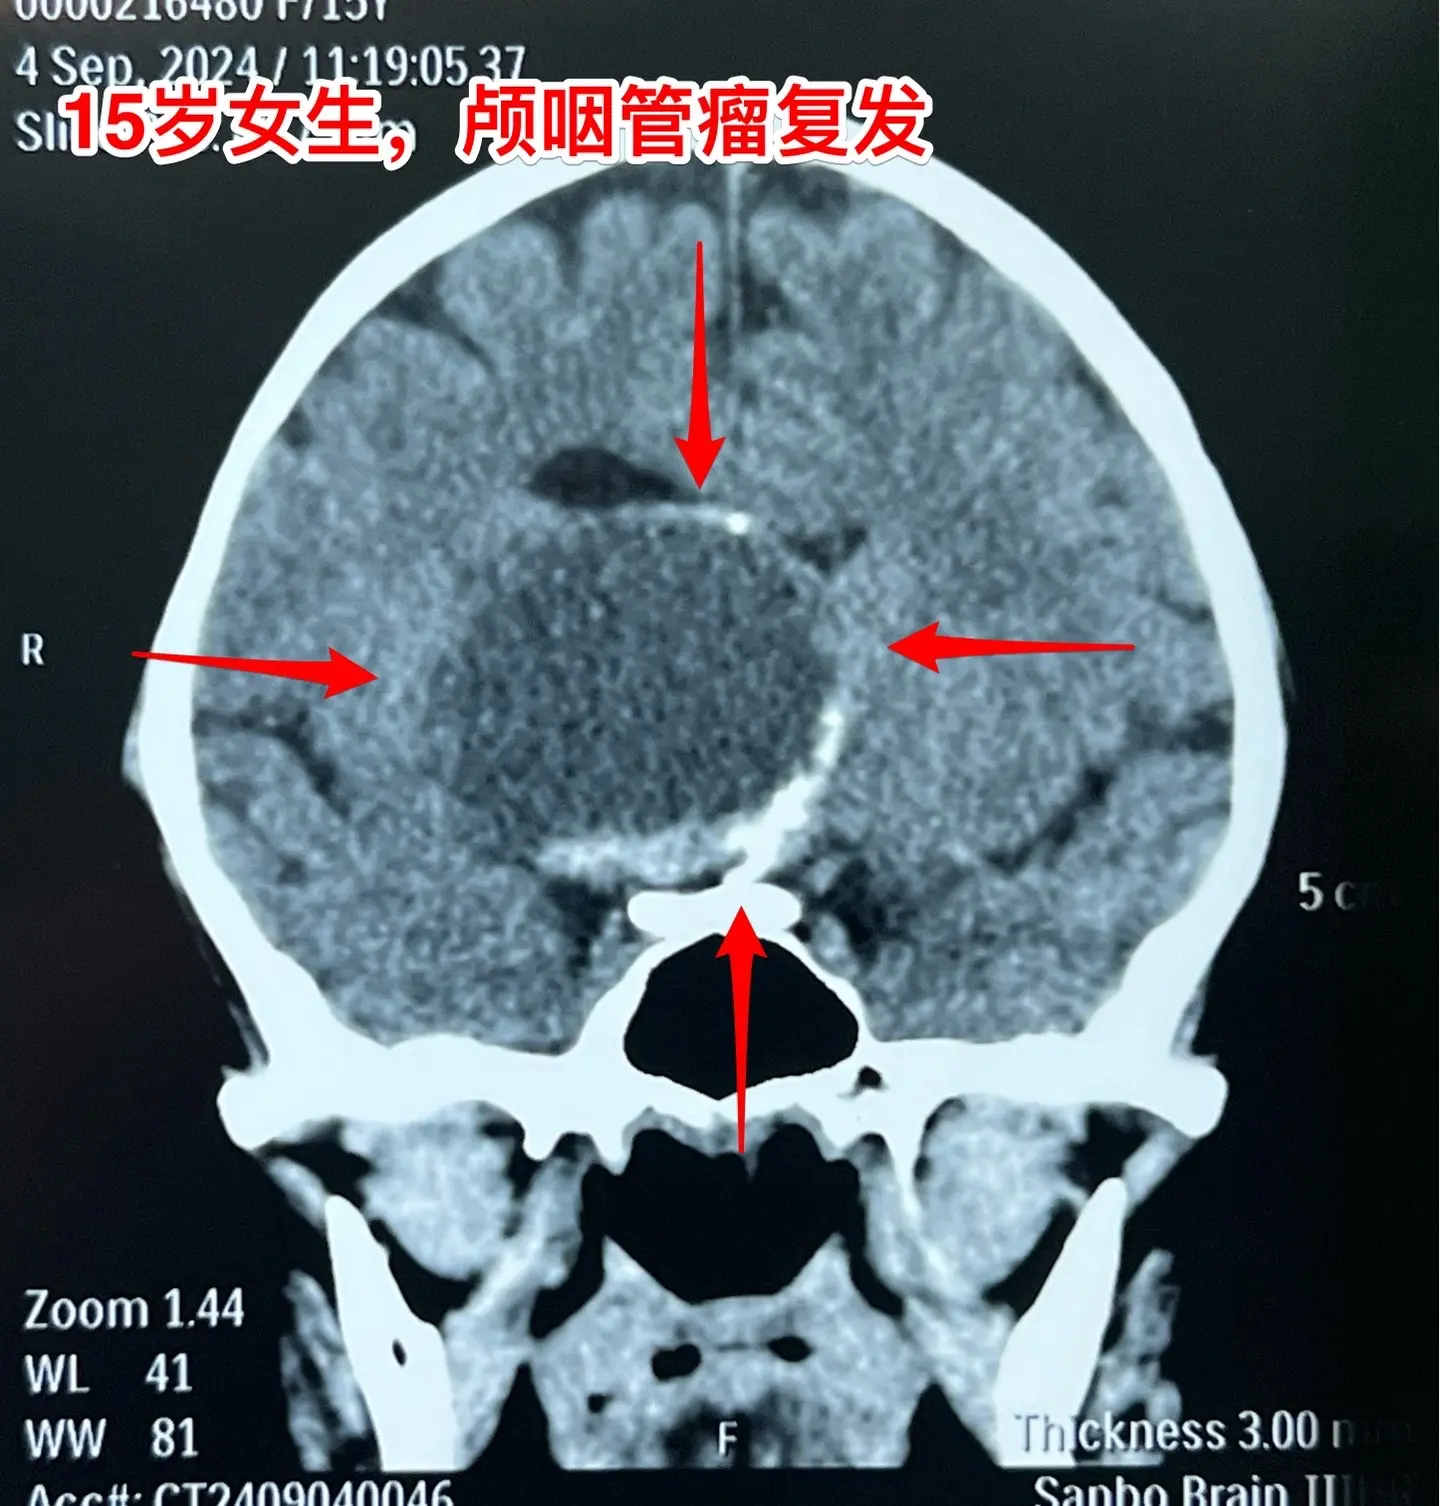

颅咽管瘤不是按匀速生长,进展很难预料。15岁的福建龙岩市女生,因颅咽管瘤之前在上海作过一次开颅手术,只有左眼有有效视力。两年前就发现肿瘤复发了,多次复查磁共振,显示肿瘤生长速度缓慢。2023.8复查磁共振见图,无明显症状,家长主张继续观察。今年八月患者出现症状,复查磁共振显示肿瘤体积显著增大,见图。所以说,颅咽管瘤的生长速度不是匀速的,医生也无法预测疾病的进展情况。

9月11日作了手术,经纵裂入路顺利切除肿瘤。经过仔细对比之前的磁共振,找到了复发肿瘤的起源点,才确定了这个手术入路。手术后患者语言、运动能力均好。发热持续时间比较长,经用抗菌药治疗后平稳了,十一前出院了。